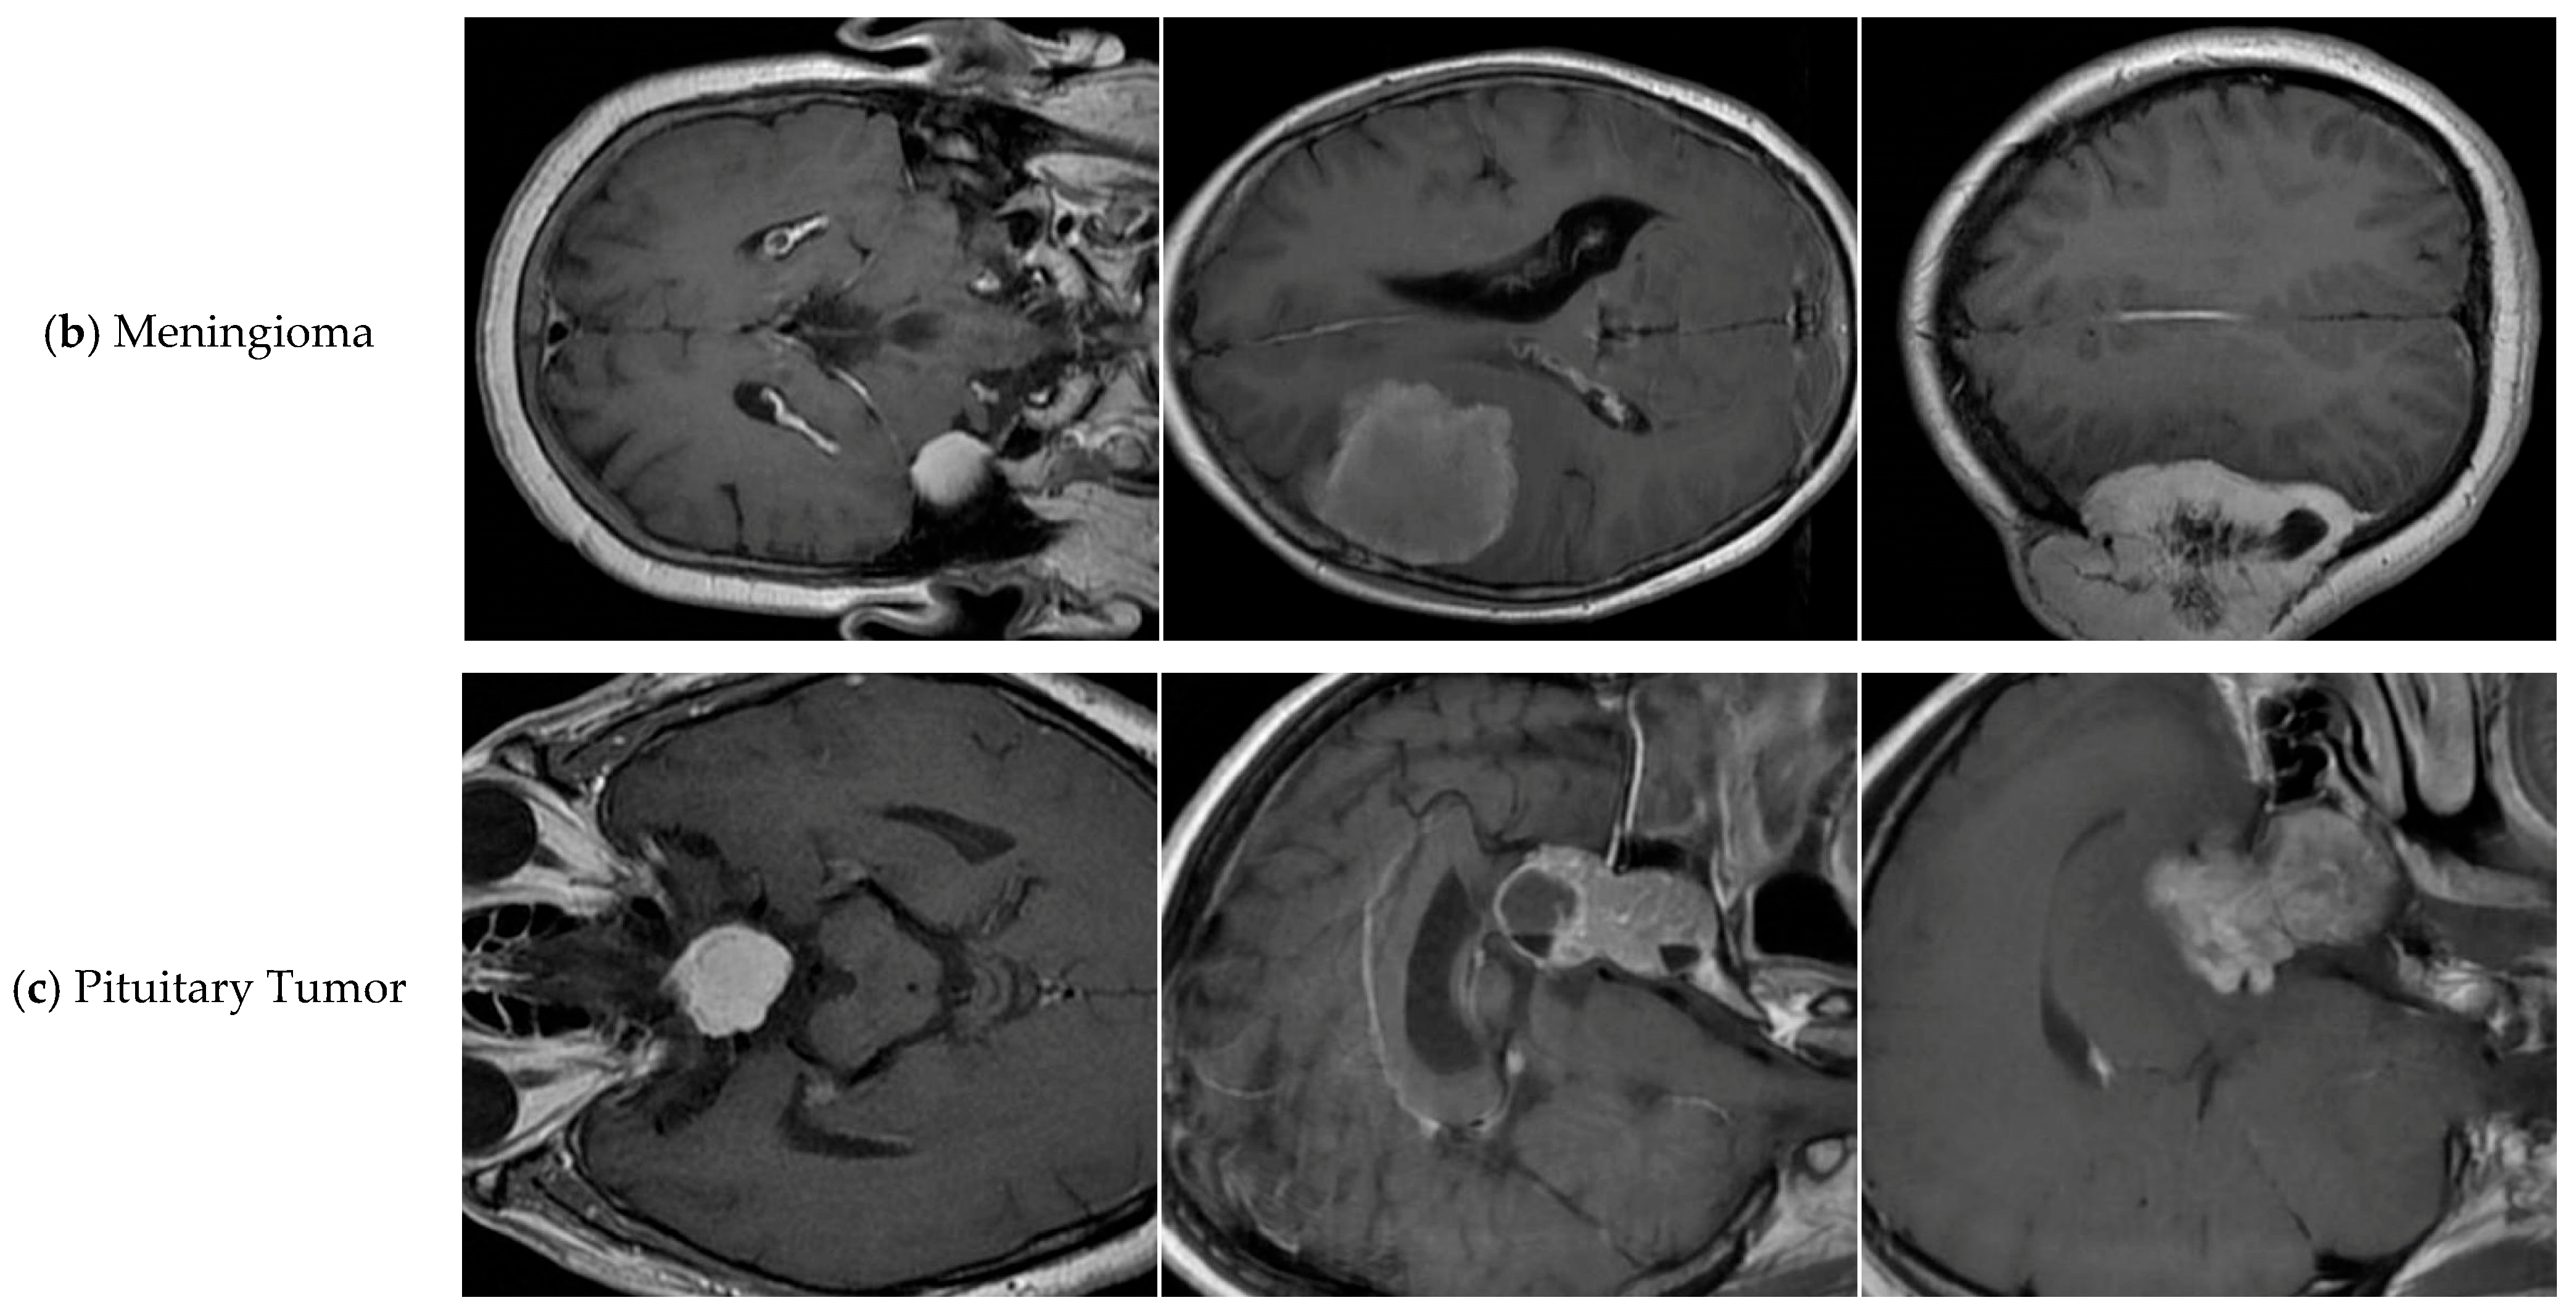

4.1. Dataset

| Tumor-Otak | Total | Glioma | Meningioma | Pituitary Tumor |

|---|---|---|---|---|

| train | 2144 | 984 | 502 | 658 |

| val | 612 | 285 | 142 | 185 |

| test | 308 | 159 | 62 | 87 |